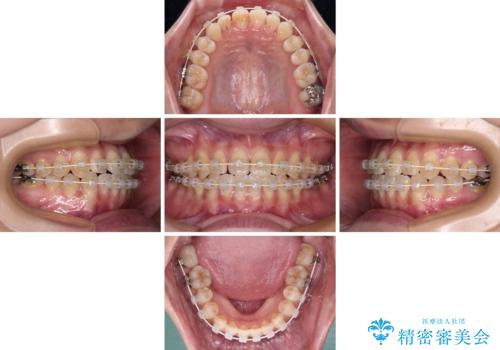

- 審美装置

- 2年

- 10-30回

マウスピース矯正も提案しましたが、しっかりと使用する自信がないとのことで、ワイヤー装置により矯正治療を行うこととしました。

クロスバイト改善まではスムーズに進みましたが、その後は強い舌の突出癖によりオープンバイトの期間が長く続きました。

舌のトレーニングをしっかりと実施してもらい、何とか仕上げることができました。